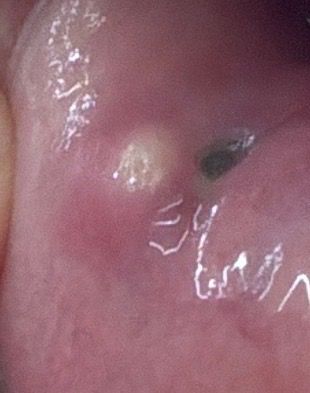

저번 주 금요일 피어싱 교체를 하며 입술 안쪽에서 동그란게 느껴졌습니다 그리고 오늘 월요일 거울로 확인을 해보니 뾰루지처럼 단단하게 올라온 노란 무언가가 있는데 병원 가서 짜내야 하는지 자연스럽게 터지기도 하는 건지 궁금합니다!

통증은 건드리면 약간 쓰리지만 평상 시 생활할 땐 모를 정도로 크지 않습니다

• 2번 째 사진